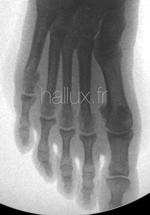

L'OSTEOTOMIE METATARSIENNE

LE TRAITEMENT CHIRUGICAL DU SYNDROME DU DEUXIEME RAYON

repose le plus souvent sur...

....une ostéotomie du deuxième métatarsien, selon la technique de Weil, souvent étendue au métatarsien adjacent voire aux autres métatarsiens latéraux selon leur forme et leur longueur, de façon à conserver une courbe harmonieuse.

Le but de cette ostéotomie et de corriger les troubles d'appui par un raccourcissement du métatarsien...

Elle peut être réalisée par technique conventionnelle, par voie mini-invasive ou percutanée, avec ou sans ostéosynthèse (vis).

Elle vise à redonner une courbe métatarsienne harmonieuse.